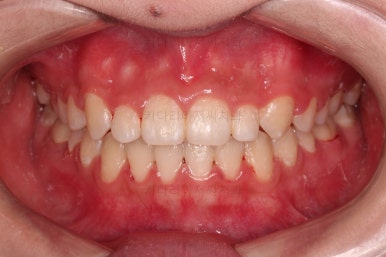

마찬가지로 초진 시 입안의 모습인데요.

위아래 앞니가 삐뚤고, 송곳니는 덧니처럼 불룩 튀어나가 있네요.

위아래 앞니는 안으로 굽어 들어와 있는 옥니(뻐드렁니 반대) 양상이었고요.

앞니 각도, 가지런한 느낌, 덧니 등 모든 점이 다 개선되었네요.

부산옥니교정 전후를 비교해 볼게요.

입안의 모습에서도 모든게 다 좋아졌고요.

웃는 모습과도 매우 조화롭게 치열이 가지런해졌네요.

앞니 각도가 개선되면서 웃을 때 보이는 치열도 가득차 보이고 환해보이고요.